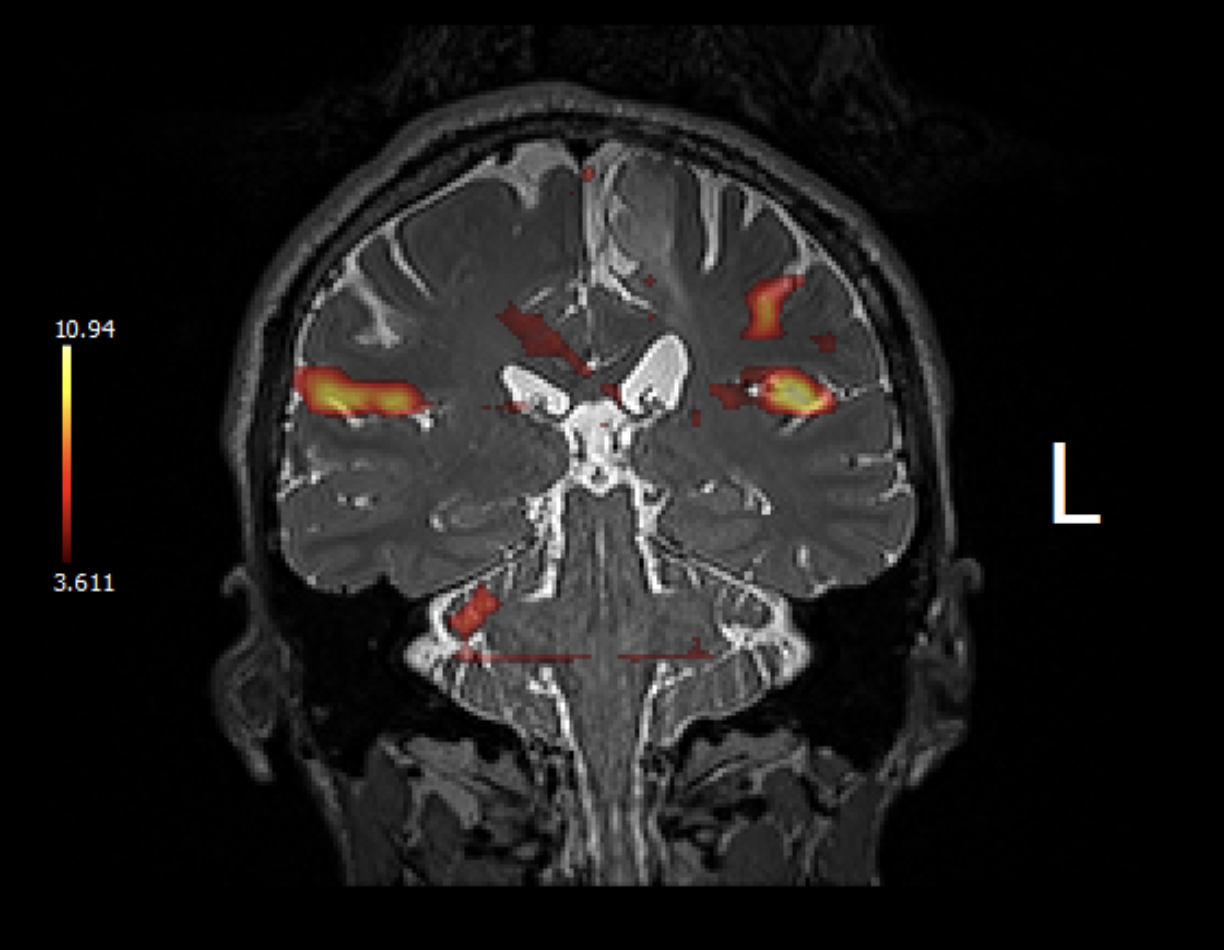

Interesting fMRI pictures (interesting note is that I was able to obtain these myself using my patient portal and scrolling through the MRI test!):

The next two images are of the technician moving my right foot, which caused my brain to light up like a Christmas tree! A lot of my foot and leg movement rewired itself when I had my first surgery in 2004. Yay for brain plasticity!